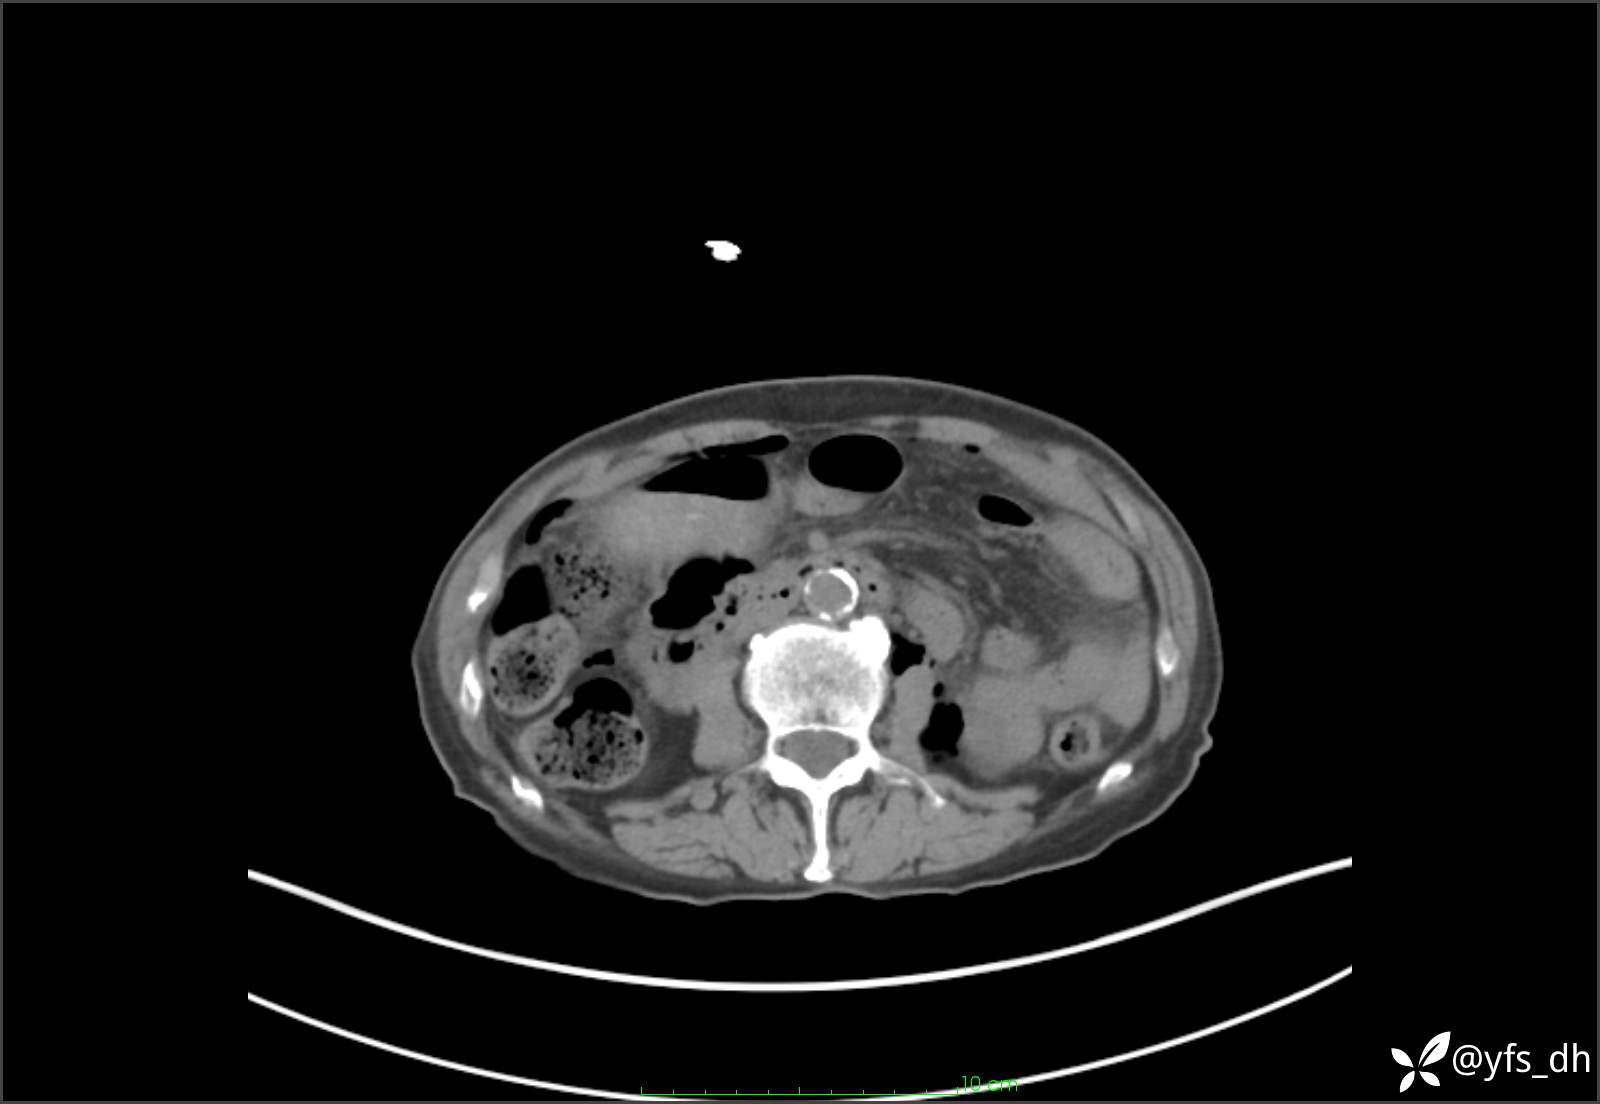

1.简要病史:患者4天前突发上腹部疼痛不适,但可以忍受。3小时前饭后突然加重,不能忍受后就诊。

2.简要手术记录:术中见腹盆腔大量肠液及粪便,乙状结肠中下段见一约3cm的破口。